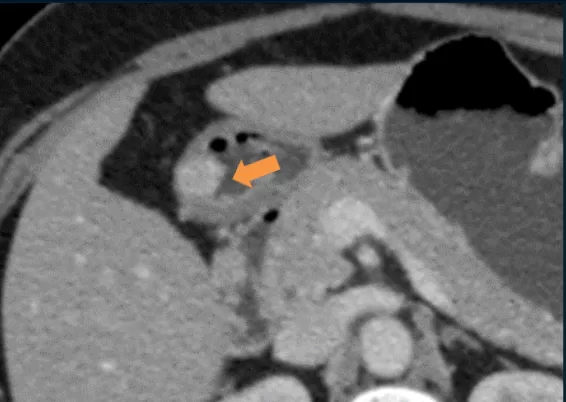

• Mulher de 40 anos

• Hipertensão, tabagismo, hipotireoidismo

• Dor abdominal difusa e intermitente, com duração de 3 meses

• Colecistectomia laparoscópica: 7 anos atrás

Cálculos biliares aderidos à parede duodenal

Colelitíase Livre na Cavidade Abdominal

-> Litíase aderida à parede duodenal: apenas alguns casos relatados na literatura